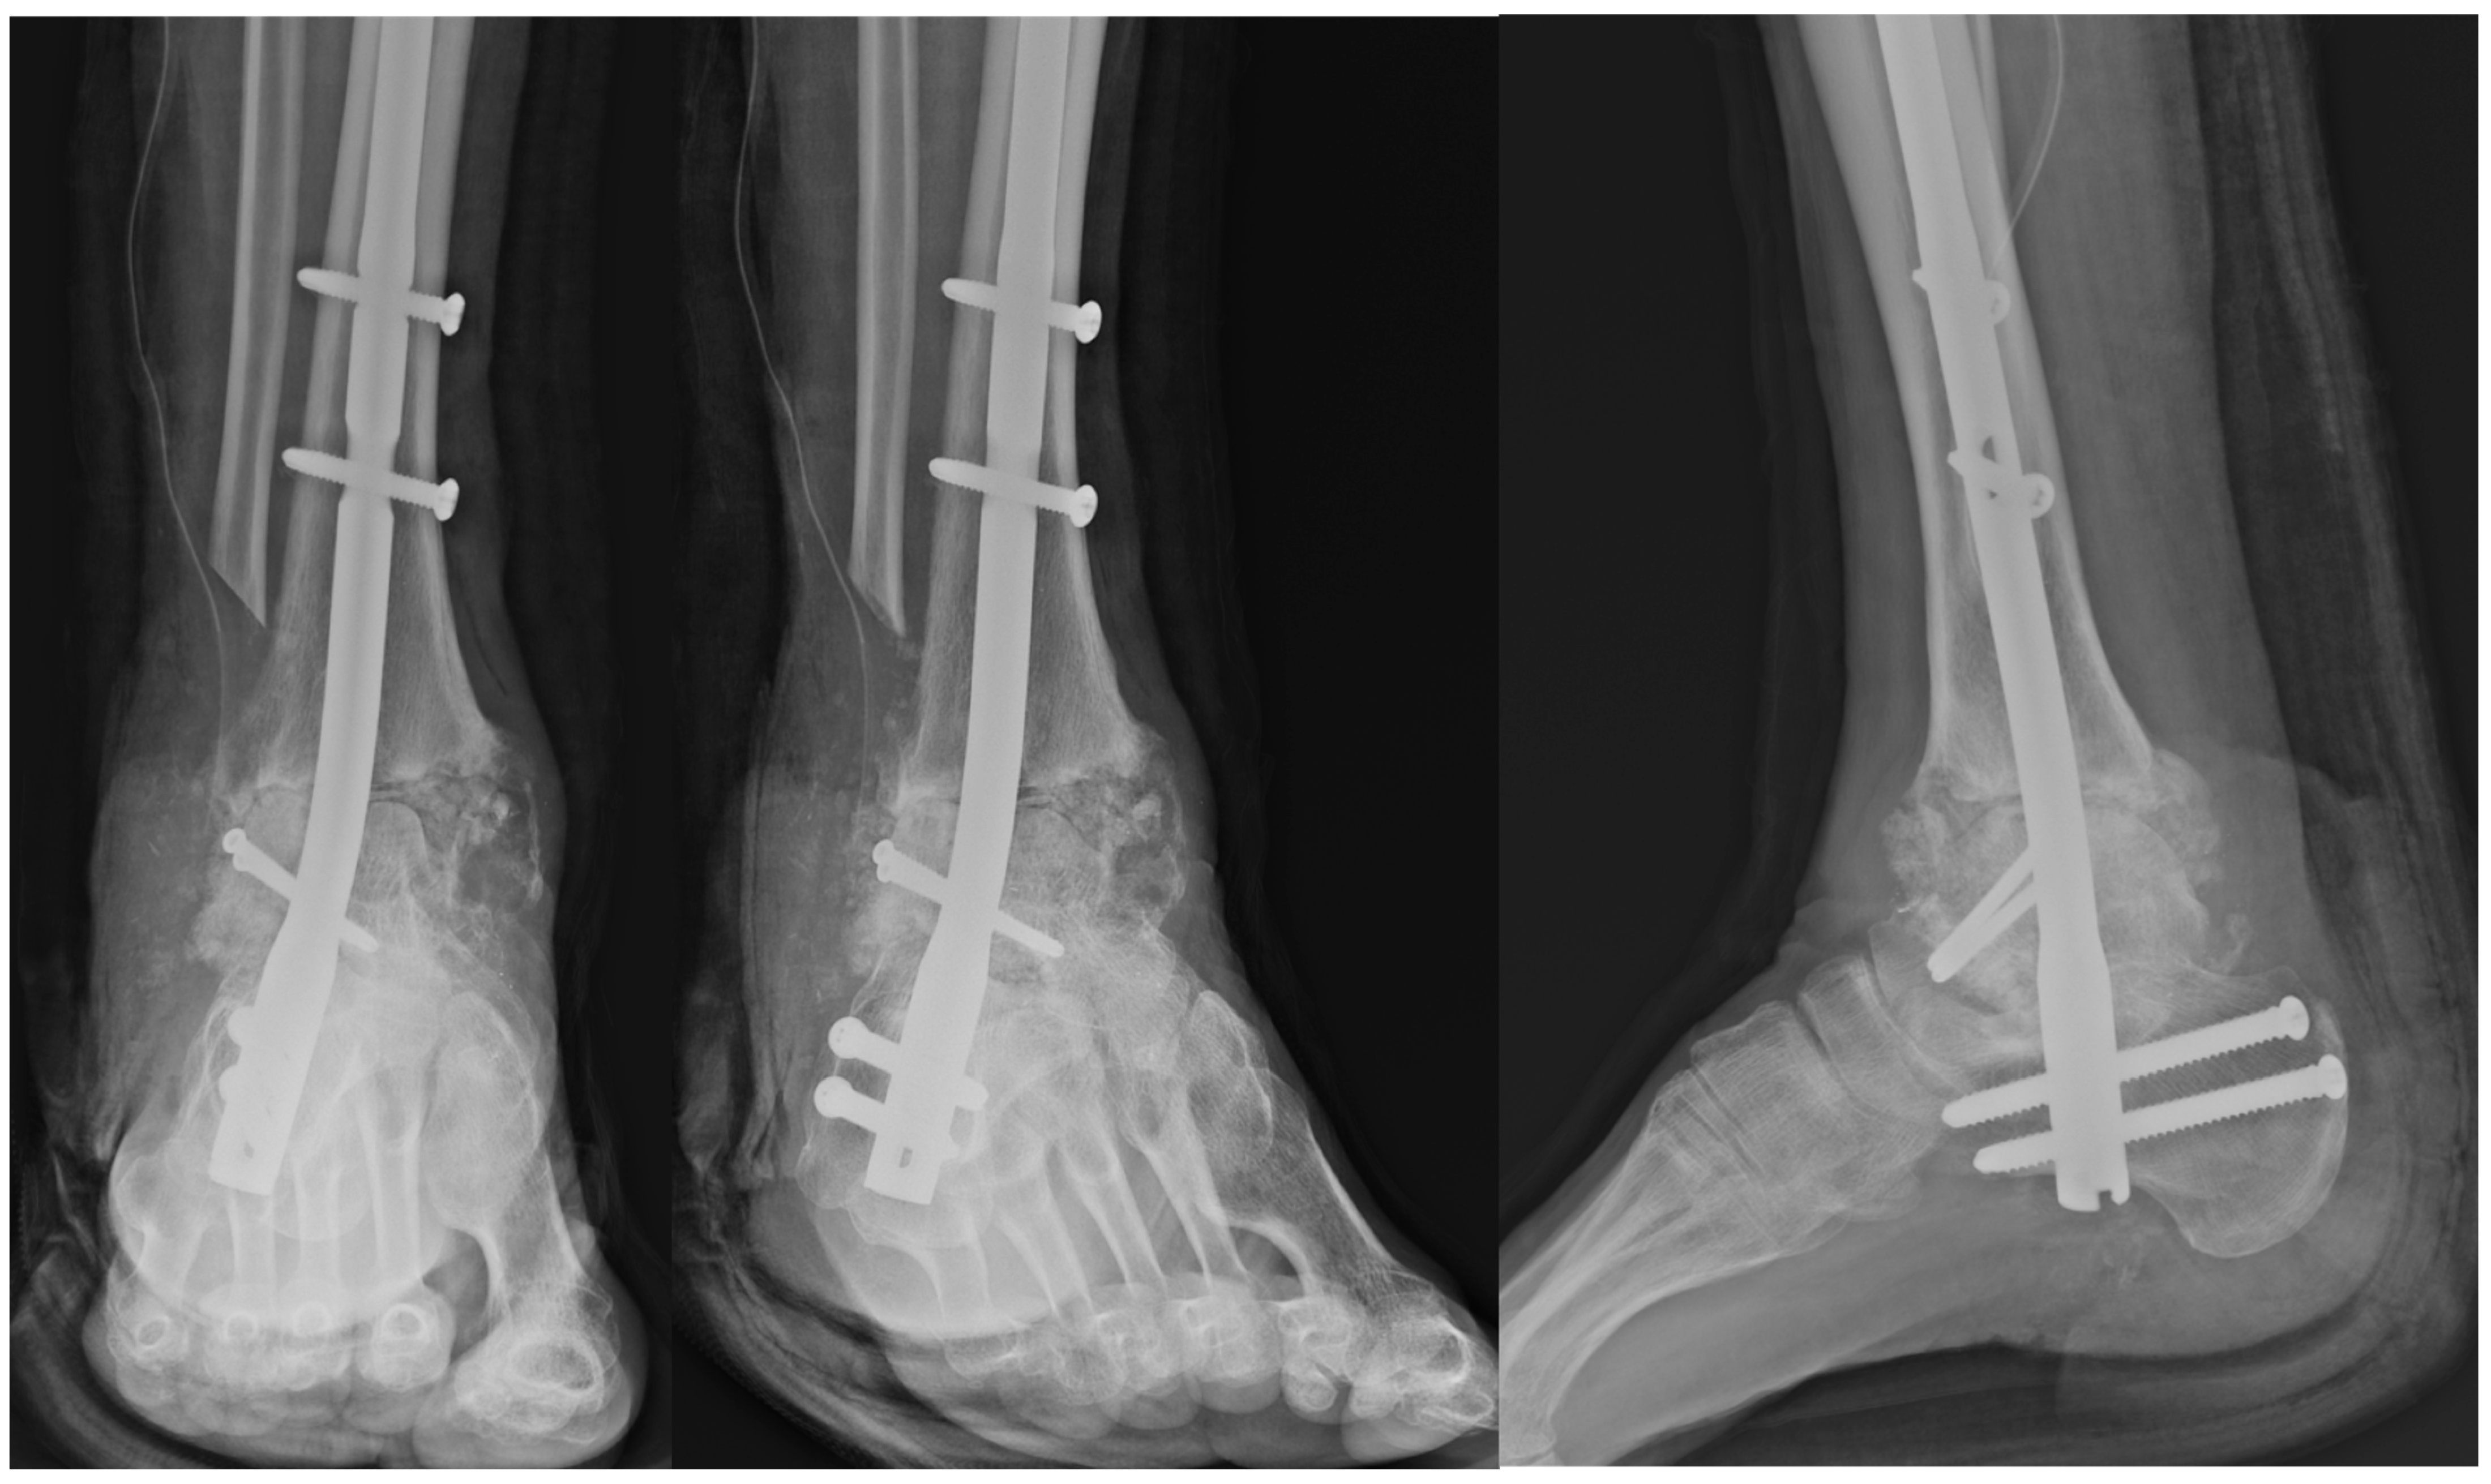

Figure 8. Two-Years Postoperative X-Ray and Computed Tomography Findings.

Successful bony union was achieved in 9 out of 11 patients (81.8%), as confirmed through serial radiographs and computed tomography (CT) scans obtained between 3 and 12 months postoperatively. Union was defined radiographically by the presence of continuous trabecular bridging across the fusion site and the absence of implant loosening or hardware failure. On CT imaging, union was defined as complete bony continuity without any radiolucent gap at the host–graft interface. Among the two patients who did not achieve complete union, one exhibited tibiotalar nonunion, and the other demonstrated subtalar nonunion.

In addition to pain relief, patients demonstrated notable functional recovery as reflected in all subscales of the Foot and Ankle Outcome Score (FAOS). The FAOS pain subscale improved from a mean of 45.2 ± 9.1 preoperatively to 72.3 ± 10.8 at two years postoperatively. Similarly, the symptoms subscale increased from 48.6 ± 8.7 to 79.4 ± 9.5, and the activities of daily living (ADL) score improved from 50.1 ± 10.2 to 75.7 ± 12.4. The sports and recreation function subscale, which is often more difficult to restore in complex foot and ankle conditions, improved from 30.4 ± 11.3 to 60.8 ± 13.7. Lastly, the quality of life (QOL) subscale rose from 34.9 ± 9.8 to 74.5 ± 12.1. All changes across FAOS domains were statistically significant (all p < 0.04), underscoring the comprehensive benefit of the procedure on both functional performance and overall well-being (Table 2).

Regarding postoperative safety, no short-term perioperative complications were observed during hospitalization or the early recovery period. Specifically, there were no cases of superficial or deep infection, soft tissue necrosis, wound dehiscence, or deep vein thrombosis (DVT). Although two cases of radiographic nonunion were noted during follow-up, neither patient experienced clinical symptoms nor required secondary surgical intervention. The absence of additional systemic or local complications further supports the viability and safety of using bulk talar allografts in TTC arthrodesis for this challenging patient population.